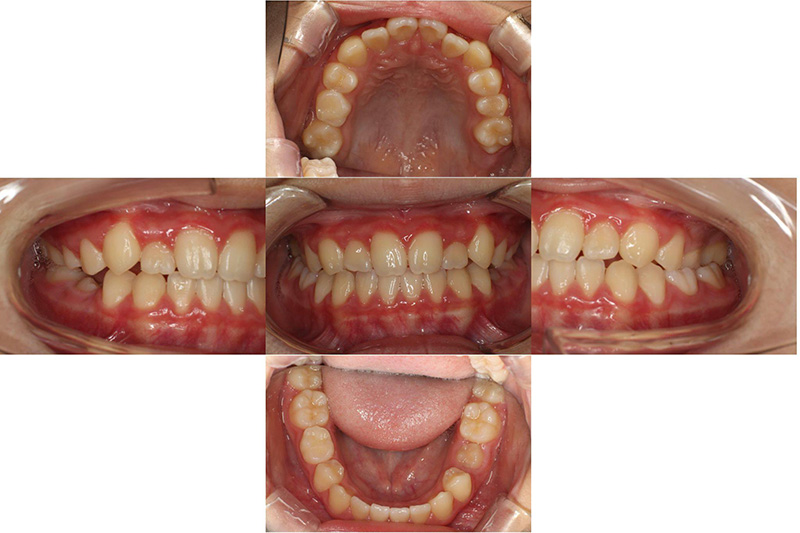

治療前

治療後

| 治療内容 | プレオルソタイプ1を日中1時間と夜間就寝時装着それに加え口腔周囲筋のトレーニング |

|---|---|

| 治療期間・回数 | 約12ヶ月、12回 |

| 費用 | 約11万円 検査費用含む |

| 副作用リスク | 後戻り 歯の痛み 歯の動揺 咬合違和感 |